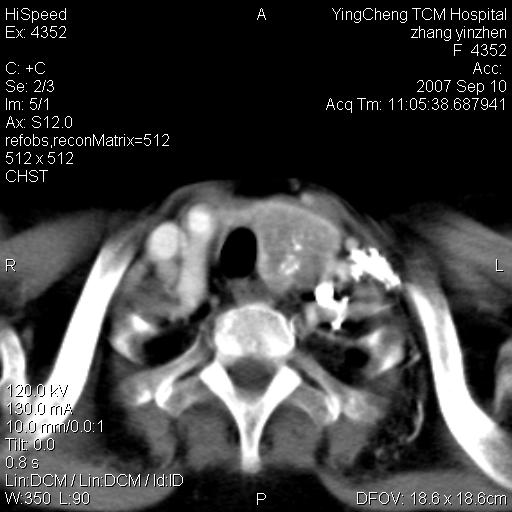

以下是引用卜一在2007-9-18 14:41:00的发言:[br]右肺肿块:毛刺+胸膜凹陷征+供血血管+浅分叶+强化。支持:周围性肺癌 !另:左侧甲状腺腺瘤!

以下是引用夏季在2007-9-18 11:00:00的发言:[br]1。右肺肿块,周围有短毛刺,肺门侧有血管与其相连,胸壁侧有胸膜凹陷征,考虑周围性肺癌 2。左侧甲状腺软组织肿块,内有高密度钙化灶,考虑左侧甲状腺腺瘤。